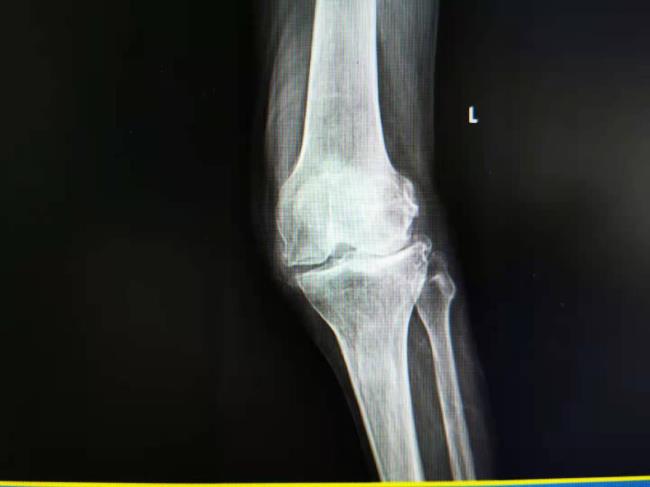

病例2:男65岁,左膝关节退行性变,关节炎,关节疼痛,活动障碍多年。

在我科行全膝关节置换手术,术后疼痛消失,功能恢复。